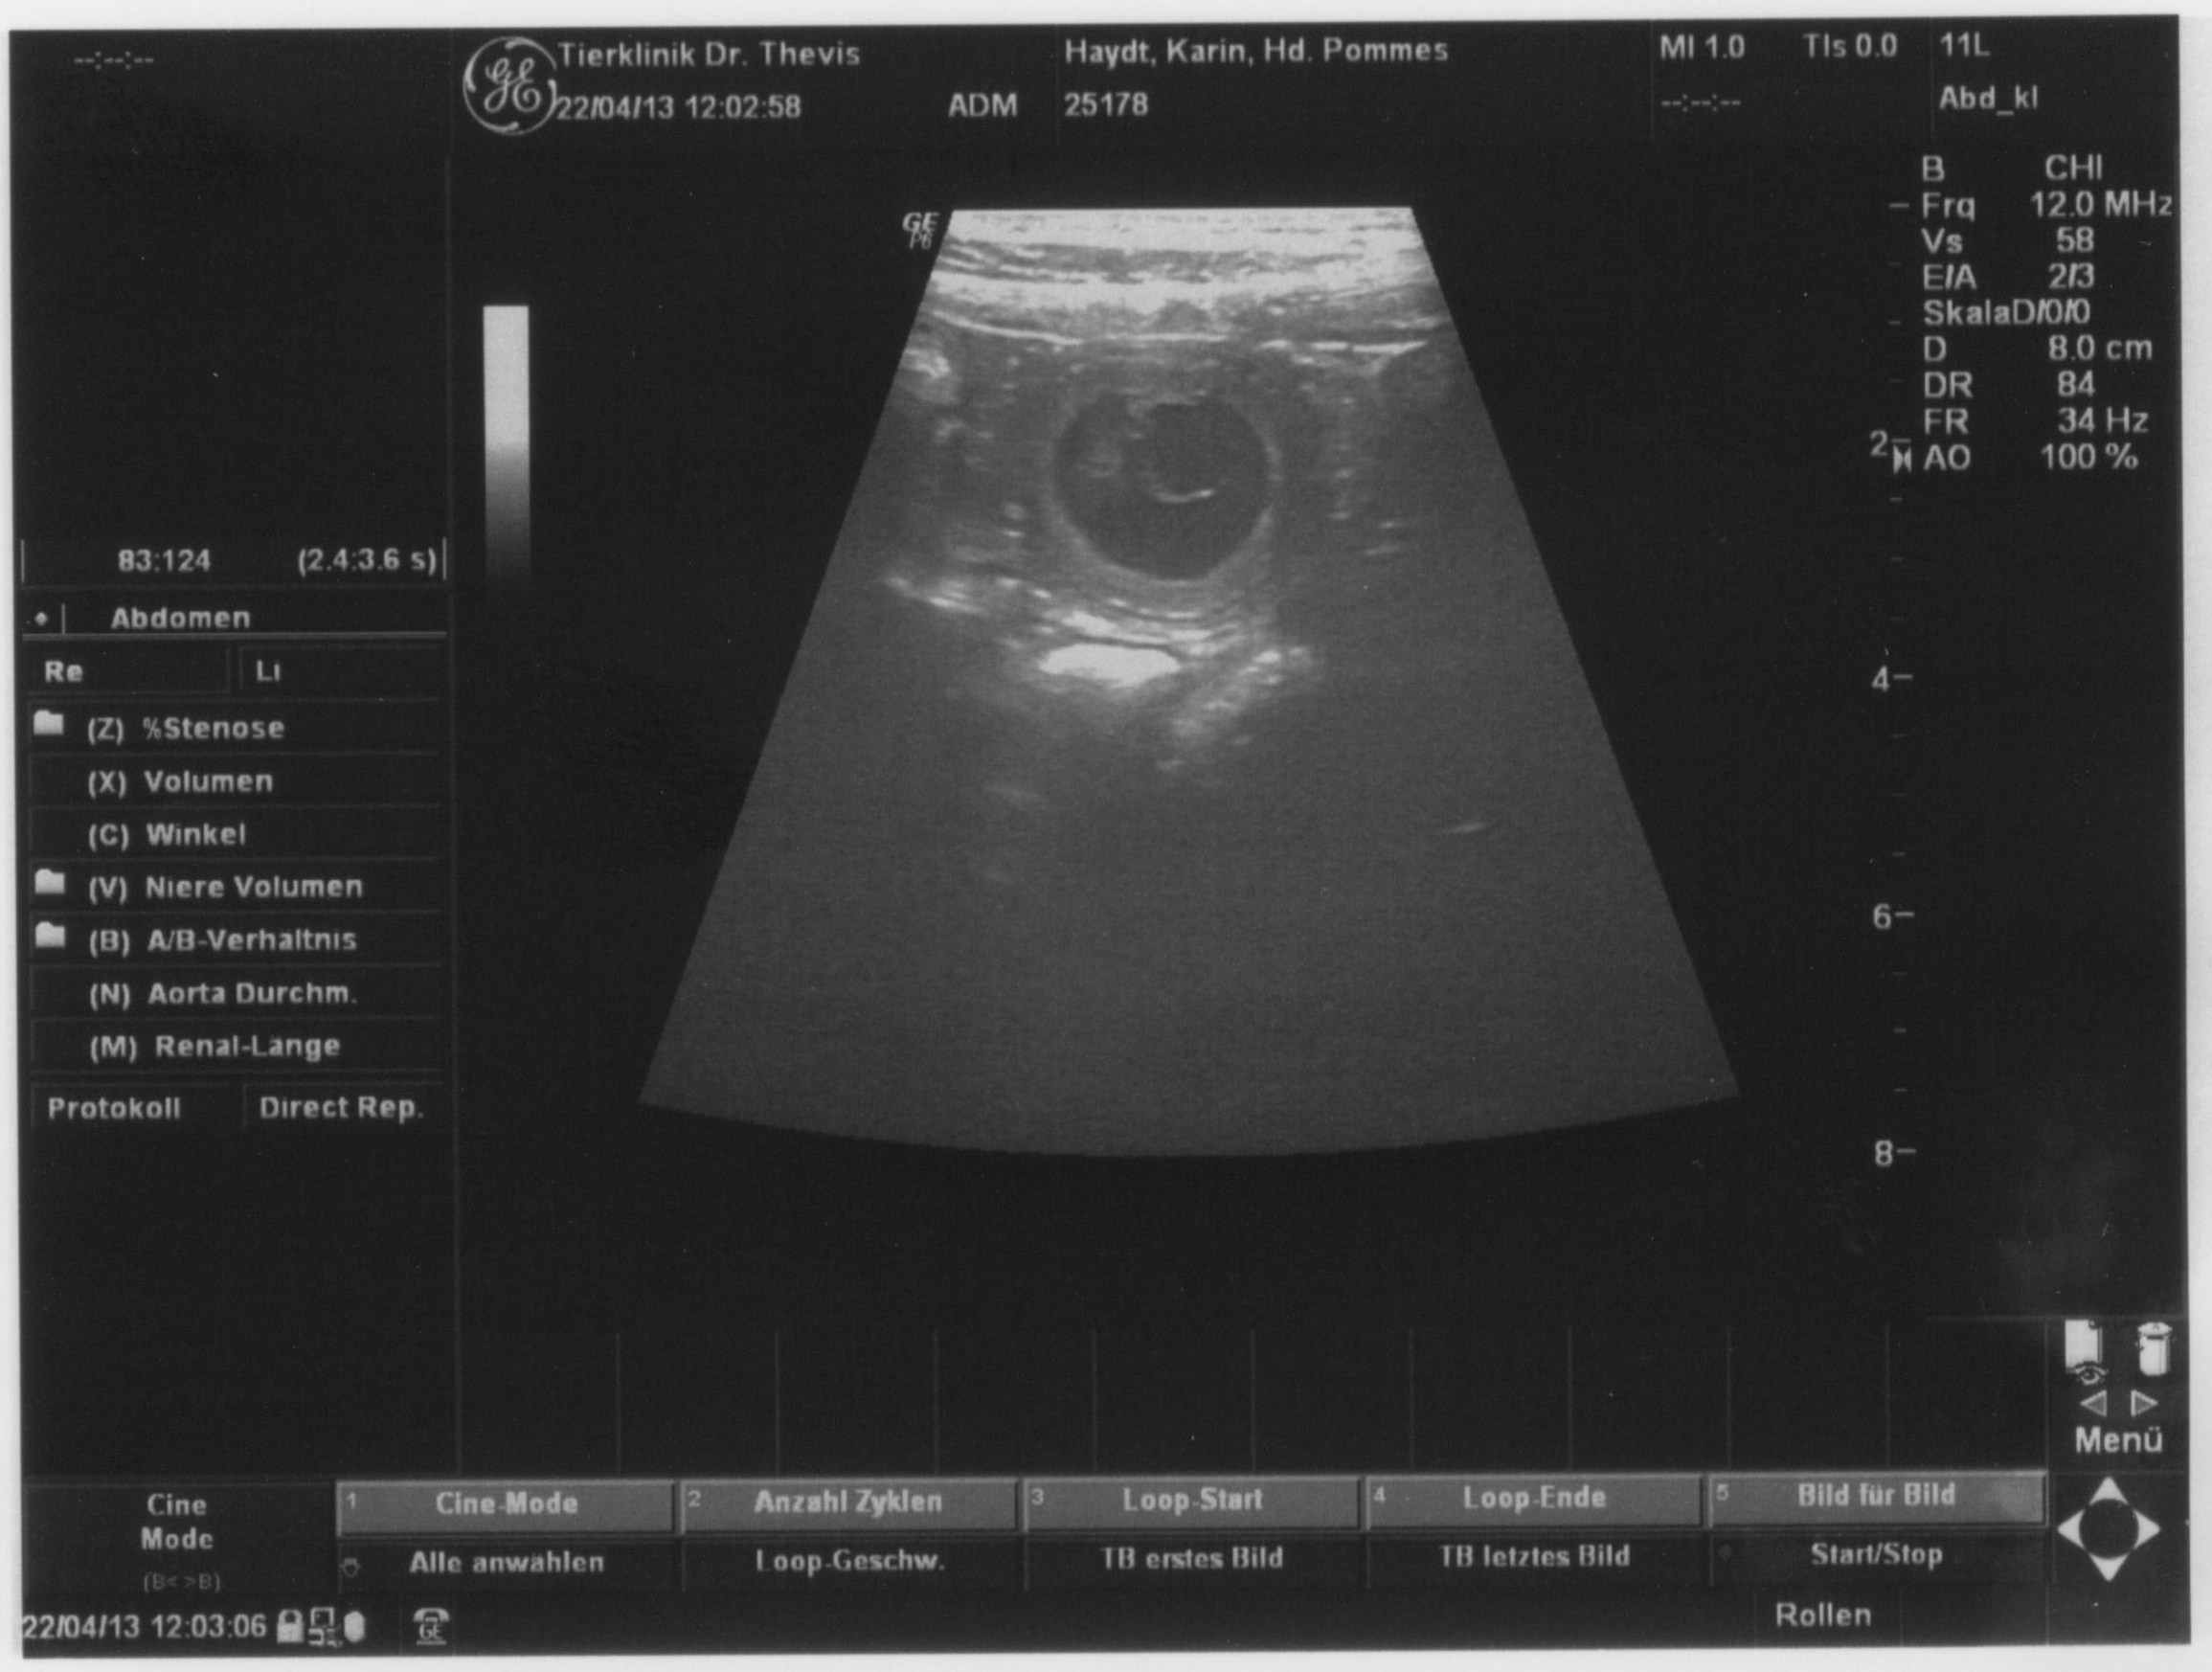

Letzte Woche waren wir beim Ultraschall und konnten mehrere Fruchtblasen erkennen.

Inzwischen kann unsere Pommes ihr süsses Geheimnis auch nicht mehr verbergen!

Wir freuen uns sehr auf die spannende Zeit, die nun vor uns liegt.